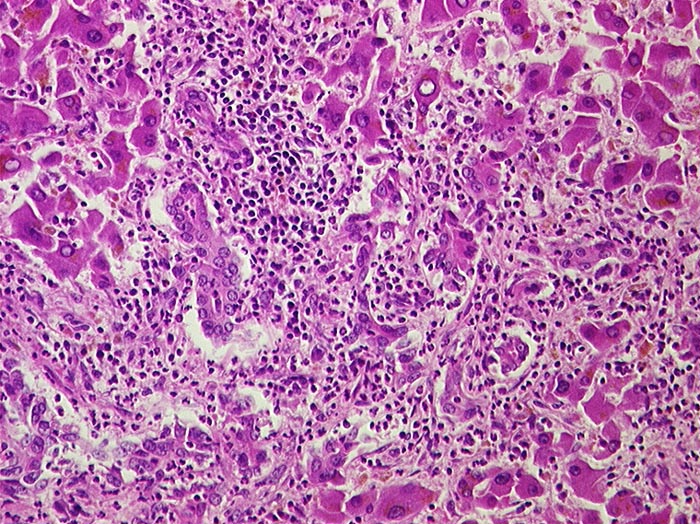

Eitrige Cholangitis

Entzündung infektiös

Leber

Portalfeld in der unteren Bildhälfte mit dichtem granulozytärem Entzündungsinfiltrat, welches auf die Gallengänge übergreift.

Metastasierendes Pankreaskarzinom mit Tumorbefall von Ductus choledochus und cysticus.